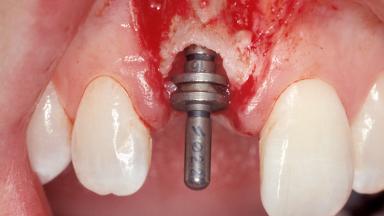

Immediate Placement of an Implant in a Maxillary Right Central Incisor Site

A 30-year-old female patient was referred to the office for the treatment of tooth 11. Her chief concern at the initial visit was to inquire, “Why is my tooth pink?” Upon clinical examination, it was determined that tooth 11 had a previous history of trauma and that the clinical crown had become noticeably pink in color as a result of internal resorption. This diagnosis was confirmed radiographically, indicating a large radiolucency involving the central and distal portions of the clinical crown. It was determined that restoration of this tooth was not possible, and that extraction was indicated. The presence of a mid-line diastema, which the patient wanted to reproduce, directed the treatment plan for tooth replacement utilizing a dental implant.

Type of Implants One-Piece|Reduced-Diameter

Attachment One-Piece|Reduced-Diameter

Abutment Type Standard

Placement Protocol Immediate implant placement

Tooth Site Maxillary incisor or canine